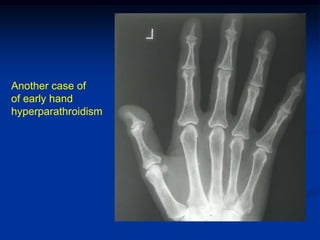

Another case of

of early hand

hyperparathroidism

Another case of ofearly hand hyperparathroidism